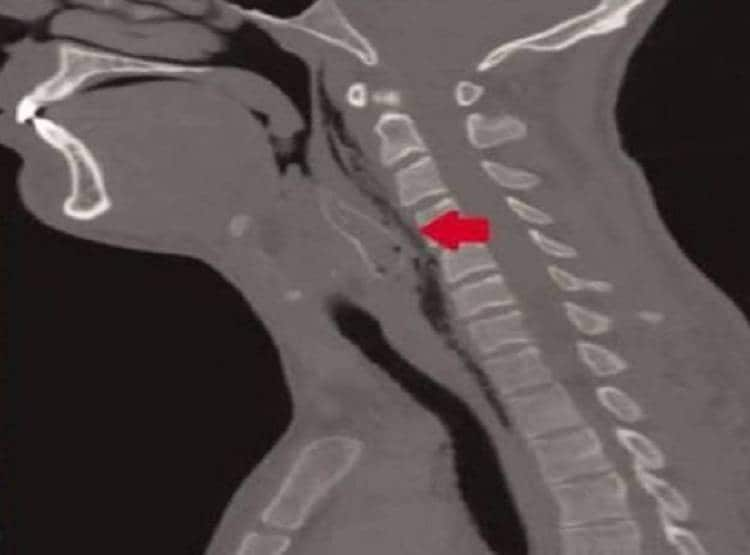

दरअसल तमिलनाडु के होसुर में एक युवक झील में मछली पकड़ने गया था. उसे वहां ही जीवित मछली को निगलते हुए टिकटॉक वीडियो बनाने का आइडिया आया. वो वीडियो बनाते हुए जीवित मछली को निगलने लगा और उसी दौरान मछली युवक के गले में फंस गई.

युवक को जब इससे सांस लेने में दिक्कत होने लगी तो उसके दोस्तों ने उसे पीठ के बल लिटाकर दबाया भी लेकिन उसे इससे कोई फायदा नहीं हुआ.

इसके बाद दोस्त उसे वहां के एक सरकारी अस्पताल ले गए जहां डॉक्टरों ने उसे मृत घोषित कर दिया. जानकारी के मुताबिक वीडियो बनाने से पहले युवक ने अपने दोस्तों के साथ मिलकर शराब का भी सेवन किया था.